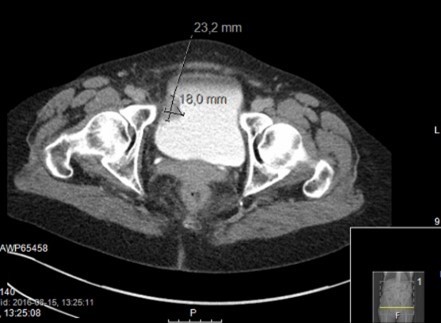

Vad ser du?

A

Förmodad urinblåsetumör